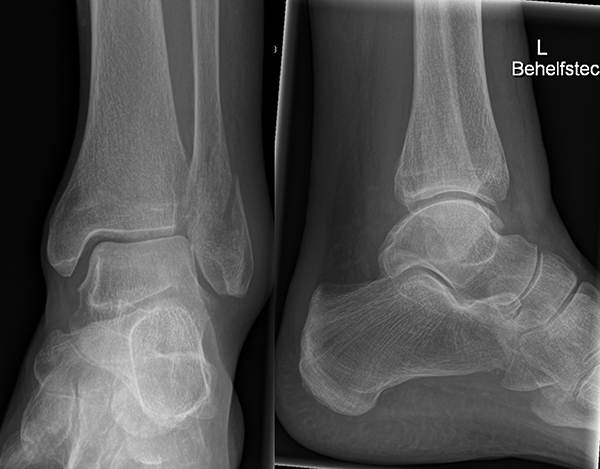

Die Standard-Röntgenaufnahmen des oberen Sprunggelenks bestehen aus drei Aufnahmen: der antero-posterioren Aufnahme (ap), der antero-posterioren Aufnahme mit Innenrotation des Unterschenkels von 20° („Mortise view“), sowie der streng seitlichen Aufnahme (siehe S2-Leitlinie Sprunggelenksfraktur). In der Röntgen-Bildgebung sollte neben den klassischen Frakturzeichen die Integrität der Syndesmose beurteilt werden. Dies erfolgt über die Beurteilung der Breite des lateralen und medialen Gelenkspalts („medial clear space“), des tibiofibularen Abstands 1cm oberhalb des OSG-Gelenkspalts („tibiofibular clear space“), bzw. der tibiofibularen Überlappung. Eine Verbreiterung des tibiofibularen Abstands über 5 mm oder die Erweiterung des medialen Gelenkspalts können Zeichen einer begleitenden Syndesmosenverletzung sein. (Abbildung 3) 6.

Liegt eine Fraktur des oberen Sprunggelenks vor, ist sowohl zur Entscheidung für ein konservatives oder operatives Vorgehen, als auch zur Operationsplanung, ein ausreichendes Verständnis der Fraktur und ihrer Morphologie notwendig. Insbesondere bei komplexen Verletzungen ist dafür die konventionelle Röntgenaufnahme in vielen Fällen nicht ausreichend. So konnten z.B. Black et al. zeigen, dass die operative Strategie zur Versorgung von OSG-Frakturen in 24% basierend auf einer zusätzlichen CT-Bildgebung relevant geändert wurden 7. Dies betraf die Lagerung, die Wahl des Zuganges und die Art der osteosynthetischen Versorgung. Besonders häufig änderte sich das Vorgehen bei Verletzungen des medialen (21%) und des posterioren Malleolus (15%). Darüber hinaus führten dislozierte (dislozierte Frakturen 31% vs. nicht-dislozierte Frakturen 20%) oder komplexe Frakturen (Trimalleolar-Frakturen 29% vs. Unimalleolar-Frakturen 10%) besonders häufig zu relevanten Änderungen des operativen Vorgehens. Die Computertomographie ist daher, insbesondere bei Bi- und Trimalleolar-Frakturen, essentiell für das Verständnis der Fraktur und somit für die Planung und Durchführung der Operation. In Abbildung 4 und 5 sind exemplarisch ein Röntgen- und ein CT Befund gegenübergestellt.